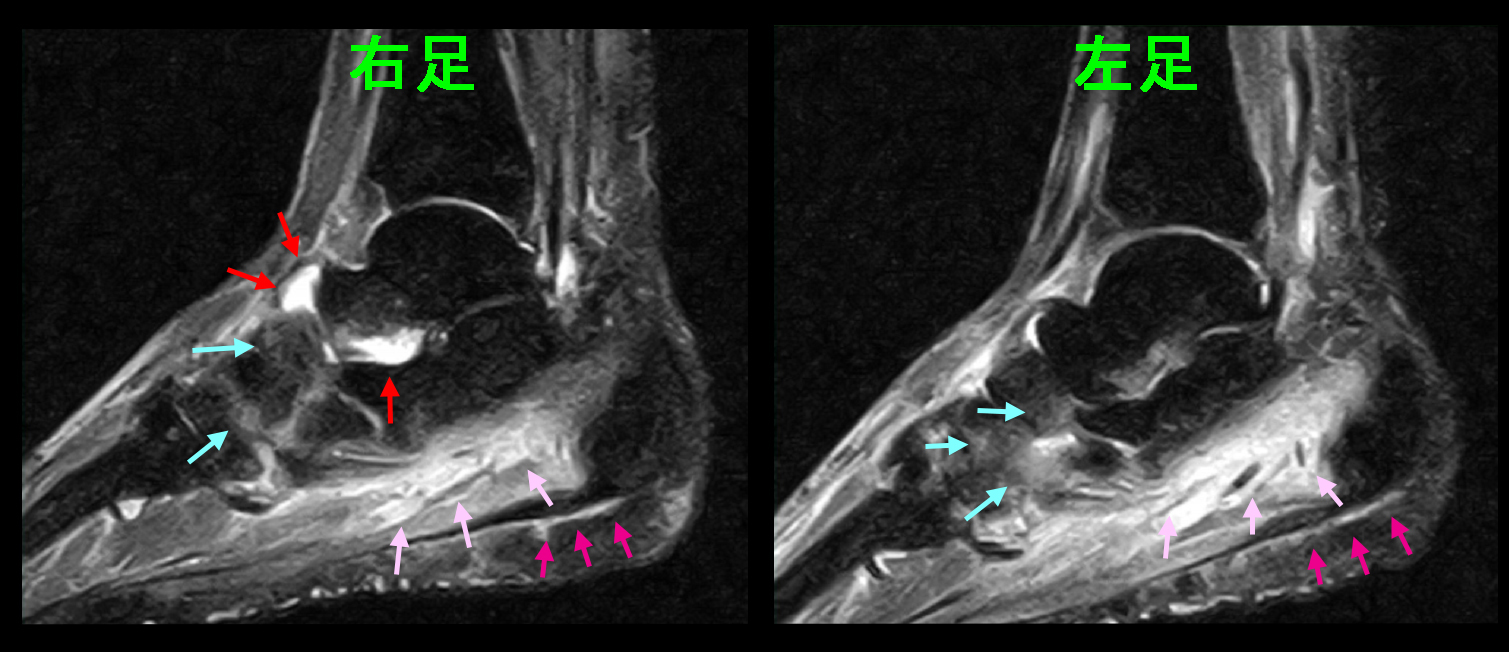

31才男 初診時MR1.jpg

両足ともかかと側の筋層が白くなっており、筋の炎症所見(ピンクの矢印)です。さらに足底側で黒い線が見え、その下側が白くなっているのは足底腱膜炎という状態となります。右足では足関節の距骨と舟状骨という骨の間で関節炎(骨の隙間が白くなっている=赤矢印)を起こしています。

31才男 初診時MR3.jpgこのMRI画像では、両側のかかとの骨(踵骨)が白くなっており、骨の炎症の所見です。(青矢印)